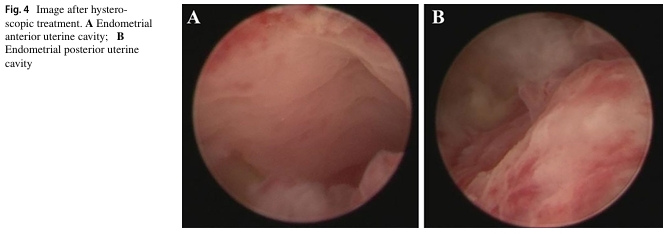

七名患者在術(shù)后進行三次自體骨髓間充質(zhì)干細胞宮腔灌注治療。兩年內(nèi)進行隨訪,子宮內(nèi)膜厚度和基底層血流量均有明顯改善,宮腔內(nèi)形態(tài)正常,且均未檢查到新的宮腔粘連癥狀。其中兩例患者在術(shù)后分別經(jīng)自然受孕和胚胎移植成功分娩。